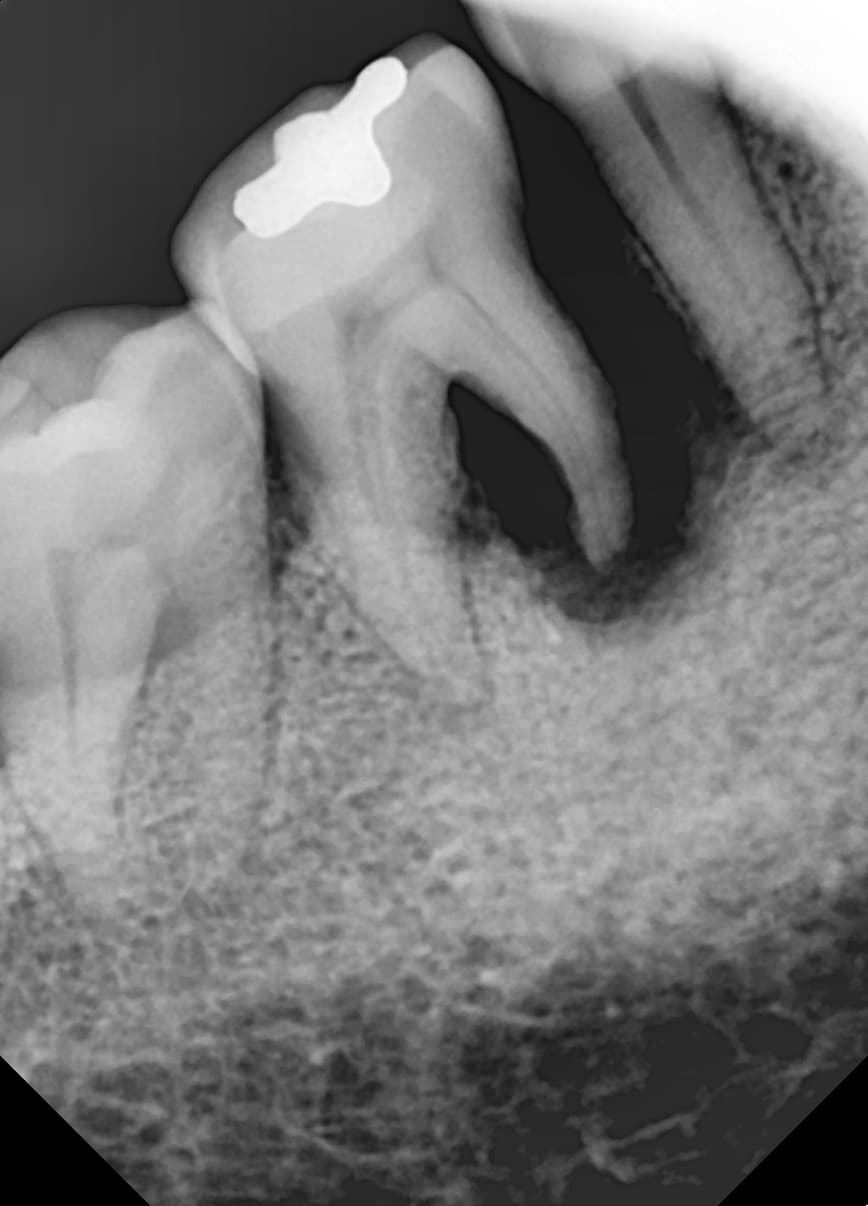

실제 치료 사례

정기적인 잇몸 치료로 임플란트 없이 건강한 치아 유지

"뼈가 심하게 녹았는데

잇몸치료로 뼈가 차올랐어요"

Before

After

심한 잇몸병으로 뼈가 많이 녹은 상태

잇몸치료와 뼈이식으로 뼈 재생 후 임플란트 식립